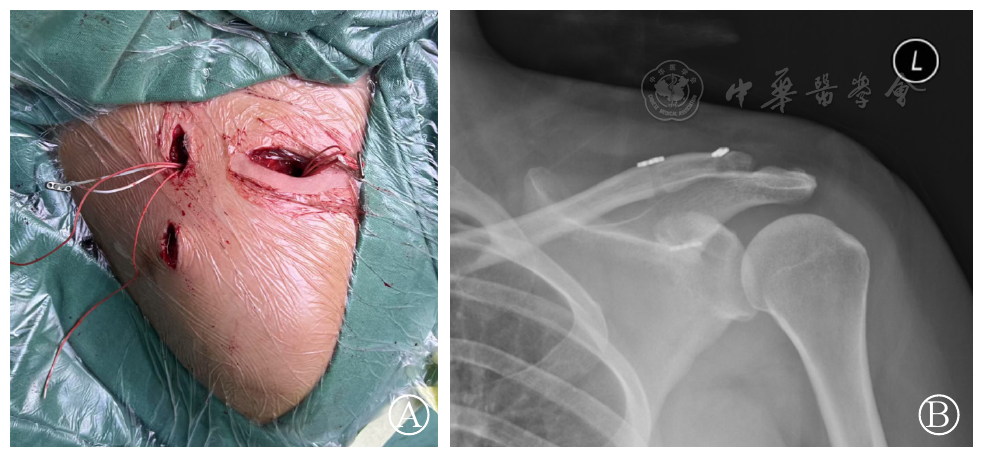

图2 带袢钛板术中(图A)与术后(图B)